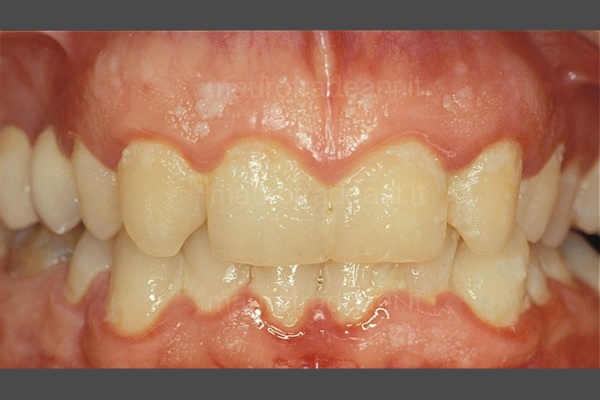

1/5: The patient presents severe dental crowding with misalignment of the lower incisors, dental shape and volume alteration with enamel wear of the gingival collars and worn incisal margins causing esthetic and functional issues. Before treating this case with prosthetic restorations, a preventive orthodontic realignment is necessary.